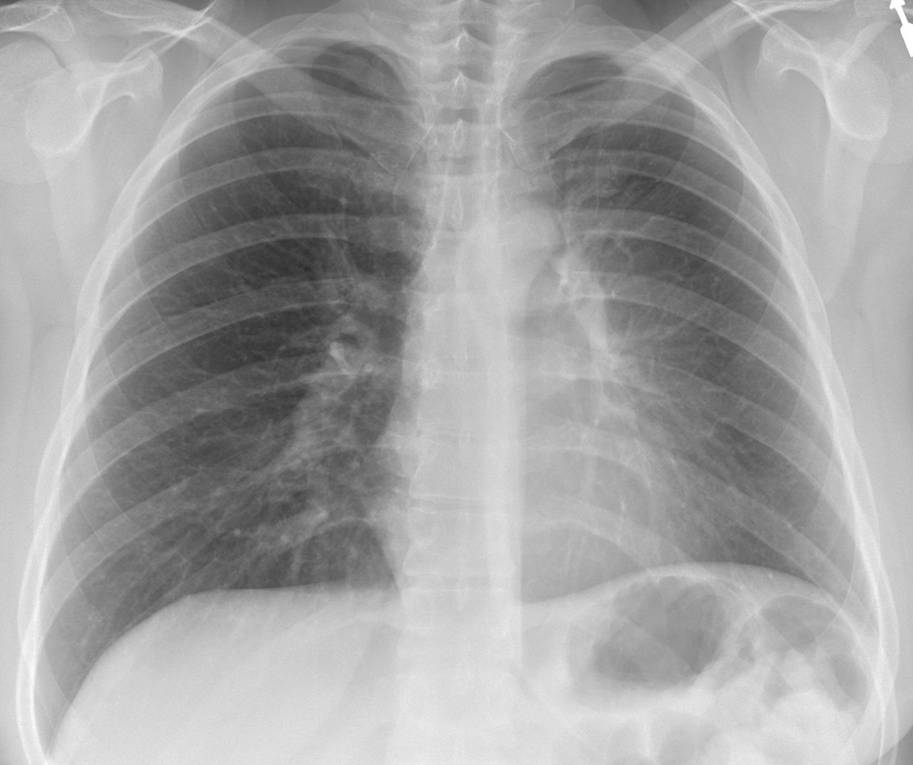

Sign? A. Hilum overlay B. Silhouette C. Air bronchogram D. Scimitar

#ChestRadEdu#meded@TanMohammedMD@DarelHeitkamp Answer: Silhouette (RML pneumonia). PA - opacity obscuring R heart border. Lateral - opacity overlying heart, marginated inferiorly by major fissurepic.twitter.com/KYSpuxPmdk